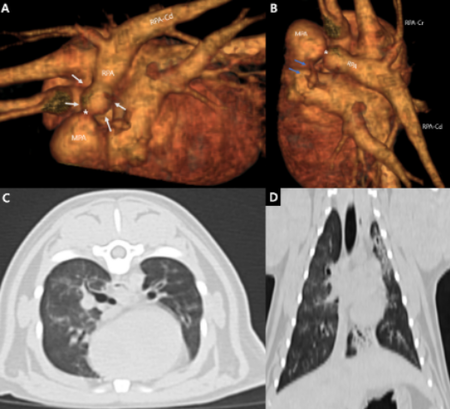

두 번째 논문은 급성 대동맥 혈전증으로 후지 마비가 발생한 개에서 stent-retriever를 이용해 혈전을 제거하고 정상 보행을 회복한 증례로 'Journal of American Animal Hospital Association(SCI)'에 게재됐다.

인의 신경계 인터벤션 시술에서 사용되는 Stent-retriever(Solitaire)를 수의학에 적용한 최초의 사례로, 혈전 제거 직후 양측 대퇴동맥의 혈류가 회복되었고, 환자는 시술 후 빠르게 자발 움직임을 보였으며, 8일 차에는 정상 보행을 회복했다. 기존의 외과적 혈전제거술이나 흡인식 혈전제거술보다 짧은 시간 내에 높은 치료 효과를 보였다는 점에서 임상적 가치가 크다.